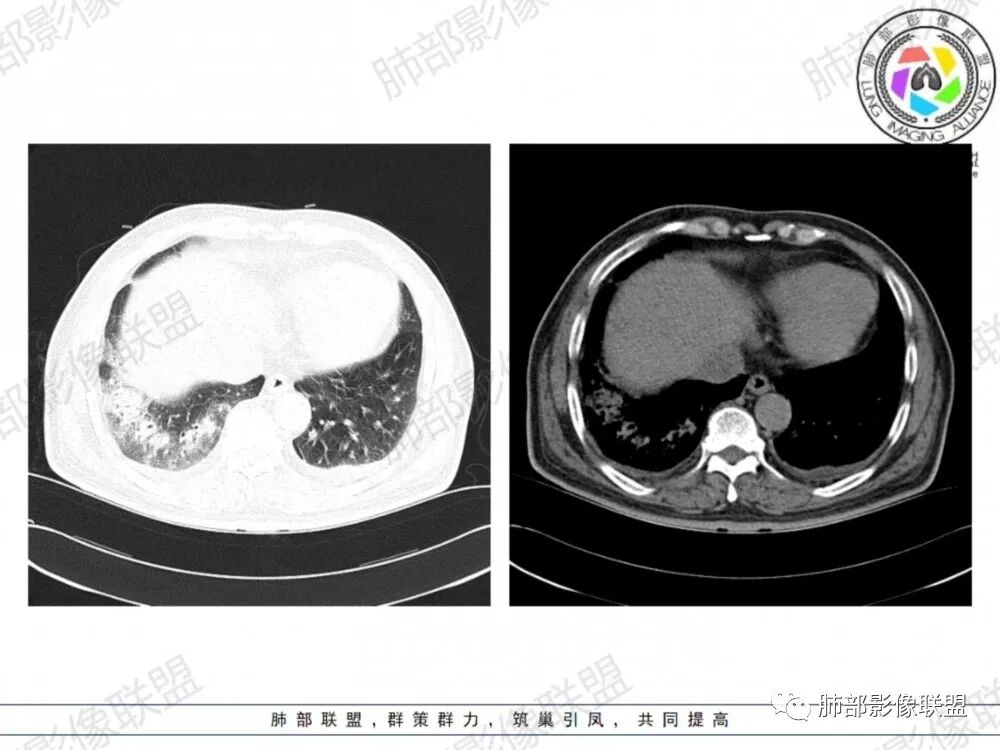

晨读:老年男性患者,咳嗽气喘3天入院,伴有发热,体温38.2℃,有糖尿病,高血压病史,有长期吸烟史,近期旅游史,白细胞,中性粒,CRP,PCT增高,肝功能损害,血气分析:低氧血症,胸部CT:双上肺及右下肺实变密度影伴周围磨玻璃密度影,边界整体清楚,内部支气管走形自然,伴双侧少量胸腔积液,综合考虑感染性病变,重症社区获得性肺炎,重点考虑非典型病原体,军团菌可能,鉴别肺克,结核合并感染

晨读老年患者,咳嗽气喘三天,腹泻,有多脏器的损害。有基础病的病史,糖尿病,高血压。旅游病史。两位靠后分布的大片状的实变影及磨玻璃样阴影,跨叶小叶性的分布,支气管充气征。内部的小叶间隔局部增厚。纵隔淋巴结不大,右侧胸腔积液。首先考虑感染性的病变,靠后重力感,肺克雷伯杆菌肺炎。鉴别诊断军团菌肺炎。

双肺多发斑片及大片状高密度影,周围伴磨玻璃影,界欠清晰,内见多发囊状透亮影呈蜂窝状,病变内支气管走形规则,无肺气肿背景,双侧胸腔积液,老年男性,糖尿病史,消化道症状,炎性指标升高,考虑军团菌感染,克雷白杆菌感染待排。

双肺大片磨玻璃影伴实变,边缘清晰,支气管通畅,磨玻璃影部分呈细网格状,胸膜下清晰,双侧胸腔积液,心影增大,心腔密度减低,贫血,考虑肺克,军团菌

胸部CT示双肺弥漫实变影伴周围磨玻璃影,跨叶段分布,可见小叶间隔增厚,支气管充气征,双侧胸腔积液。无明显坏死空洞及树芽征。

CT:双肺多叶段毛玻璃影、实变影、小叶内间质增粗,肺内病变有重力依赖趋势,双侧少量胸腔积液,无空洞、树丫;

军团菌感染可累及多个脏器,肺是主要的受侵器官。军团菌肺炎为广泛多叶分布的炎症。

1.病变复杂多样∶大片状实变影、斑片状模糊阴性,网格状阴性、小结节影。多叶受侵是本病重要影像学特征性改变。

3.呈小叶肺炎状改变,病变大小以肺小叶为单位的支气管肺炎,呈弥漫性的单或双侧分布。局部可融合呈高密度的团片状影像,本病又一典型的影像学特点。

4.病变常伴有胸水出现,肺部阴性多变的情况下伴有胸水形成应高度怀疑军团菌感染的可能。